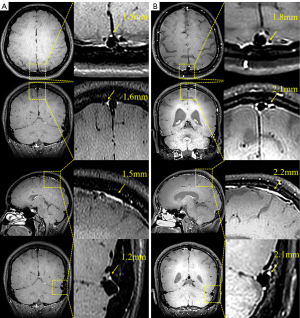

Both contrast agent-enhanced and nonenhanced BB images with the same layer thickness geometry (acquisition interval ≤30 s) were acquired, with mLVs being hyperintensive only in the enhanced BB sequences. Three blinded neuroradiologists (each with ≥6 years of experience) independently used workstation calipers (A site, 0.1 mm) to measure the largest mLV diameter within 3 cm of the superior sagittal sinus (SSS) in the most conspicuous slice identified on axial, coronal, and sagittal images; the procedure was repeated bilaterally for the transverse sinus (TS) (Figure 2). For each lesion, the thickest perisinus mLV within 10 mm of the tumor margin was similarly measured, which served as the regional mLV diameter (Figure S1). Each observer repeated the measurements after a 2-week interval to determine the intraclass correlation coefficient (ICC), with an ICC ≥0.90 indicating reproducibility. The primary outcome was favorable treatment response (FTR), defined as stable disease (SD) or partial response (PR) at 6 months after therapy initiation, assessed according to immune Response Evaluation Criteria in Solid Tumors (iRECIST). Progressive disease (PD) was considered an unfavorable outcome (Figure 3).

Figure 2 The process of mLV measurement in the BM and non-BM groups. (A) mLV measurements with the BB sequence in a patient without BMs. (B) mLV measurement with the BB sequence in a patient with BMs. The yellow arrows in the figure indicate the thickest points of the mLV. BB, black-blood; BM, brain metastasis; mLV, meningeal lymphatic vessel.

Figure 3 Typical example from each of the SD + PR group and the PD group. (A) Comparison of mLV diameter measurements before and after treatment in a patient with brain metastases in the PD group. (B) Comparison of mLV diameter measurements before and after treatment in a patient with brain metastases in the PR group. The yellow arrows in the figure indicate the thickest points of the mLV. mLV, meningeal lymphatic vessel; PD, progressive disease; PR, partial response; SD, stable disease.